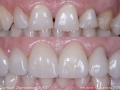

As Facetas Cerâmicas (lentes de contacto dentárias ou laminados), permitem corrigir da maneira mais estética e conservadora possível, problemas de forma e tamanho, côr e posição dos dentes, bem como substituir restaurações antigas e inestéticas.

São aderidas químicamente ao esmalte dentário de uma forma permanente, com o objectivo de melhorar a estética dos nossos pacientes.